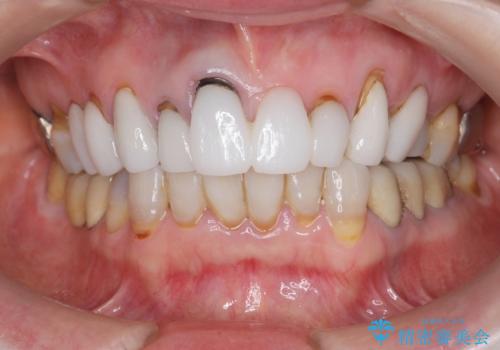

[ セラミック治療 ] 歯ぐきの際の黒ずみを改善したい

- 歯ぐきとセラミックの間の黒ずみが目立つので、きれいに治してほしい。と希望され来院されました。

歯ぐきの位置が変化しクラウン下の歯が見えるようになってしまったことで、審美障害が生じている状態です。

クラウンマージンの再設定を行うことで、黒ずんだ部分を再度覆い、審美障害を改善します。

- 52.8万円(ジルコニアクラウン×4・仮歯×4)費用は治療当時の料金となります